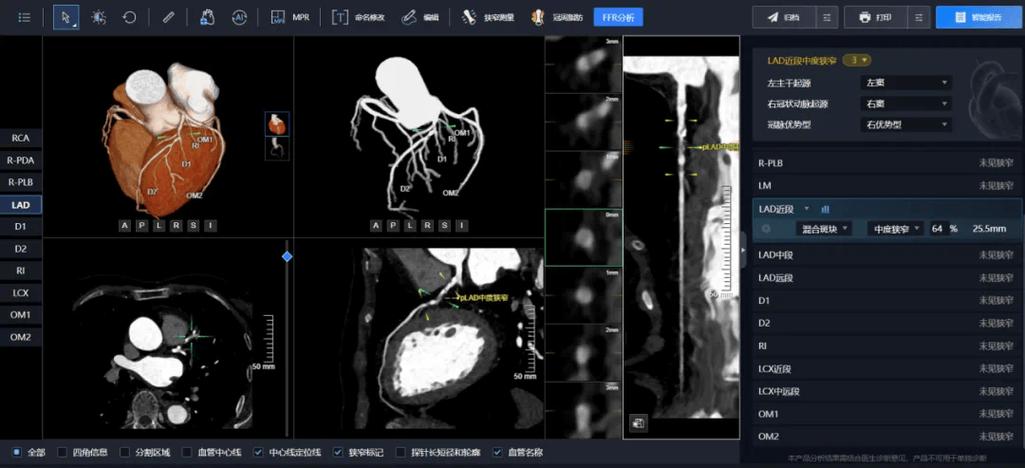

| CT | 肺癌(肺结节检测与良恶性判断)、脑卒中(出血/缺血)、冠状动脉钙化评分、肝脏/胰腺肿瘤 | 精准分割病灶(圈出病变范围)、量化分析(如结节体积、密度变化)、预测良恶性,辅助制定手术方案。 |

实现量化与精准分析:

AI不仅能“发现”病灶,还能“量化”病灶,它可以精确计算肿瘤的体积、密度、形状变化,为疗效评估和预后判断提供客观、可重复的数据指标。